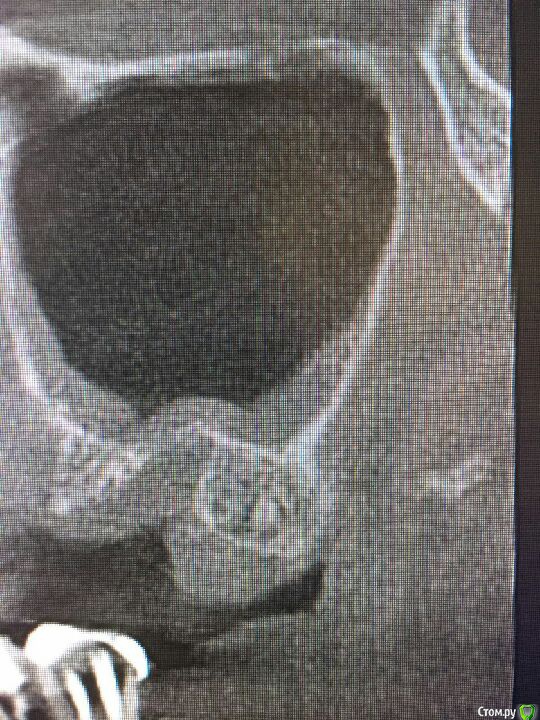

Musya31 Опубликовано 23 января, 2017 Поделиться Опубликовано 23 января, 2017 (изменено) Верх справа. Не помню, чтобы удаляла 8-ку. Это сидит видимо давно. Долго разбираюсь с болями в правой части лица, челюсти. Может быть причина здесь? Нужно удалять, как считаете? И трудным ли будет удаление? Ну и до кучи: нижняя справа семерка. Можно ли попытаться спасти? От нее тоже может болеть? Всем спасибо! Изменено 23 января, 2017 пользователем Musya31 Ссылка на комментарий